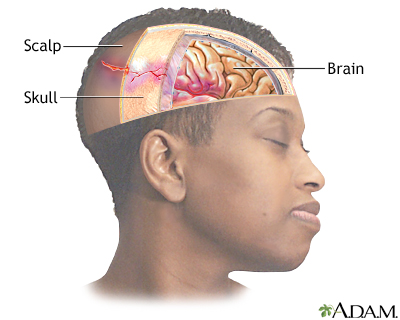

A head injury is any trauma to the scalp, skull, or brain.

Head injury can be either closed or open (penetrating).

- A closed head injury means you received a hard blow to the head from striking an object, but the object did not penetrate the skull.

- An open, or penetrating, head injury means you were hit with an object that broke the skull and entered the brain. This is more likely to happen when you move at a high speed, such as going through the windshield during a car accident. It can also happen from a gunshot to the head.

Head injuries may cause bleeding:

- In the brain tissue

- In the layers that surround the brain (subarachnoid hemorrhage, subdural hematoma, epidural hematoma)